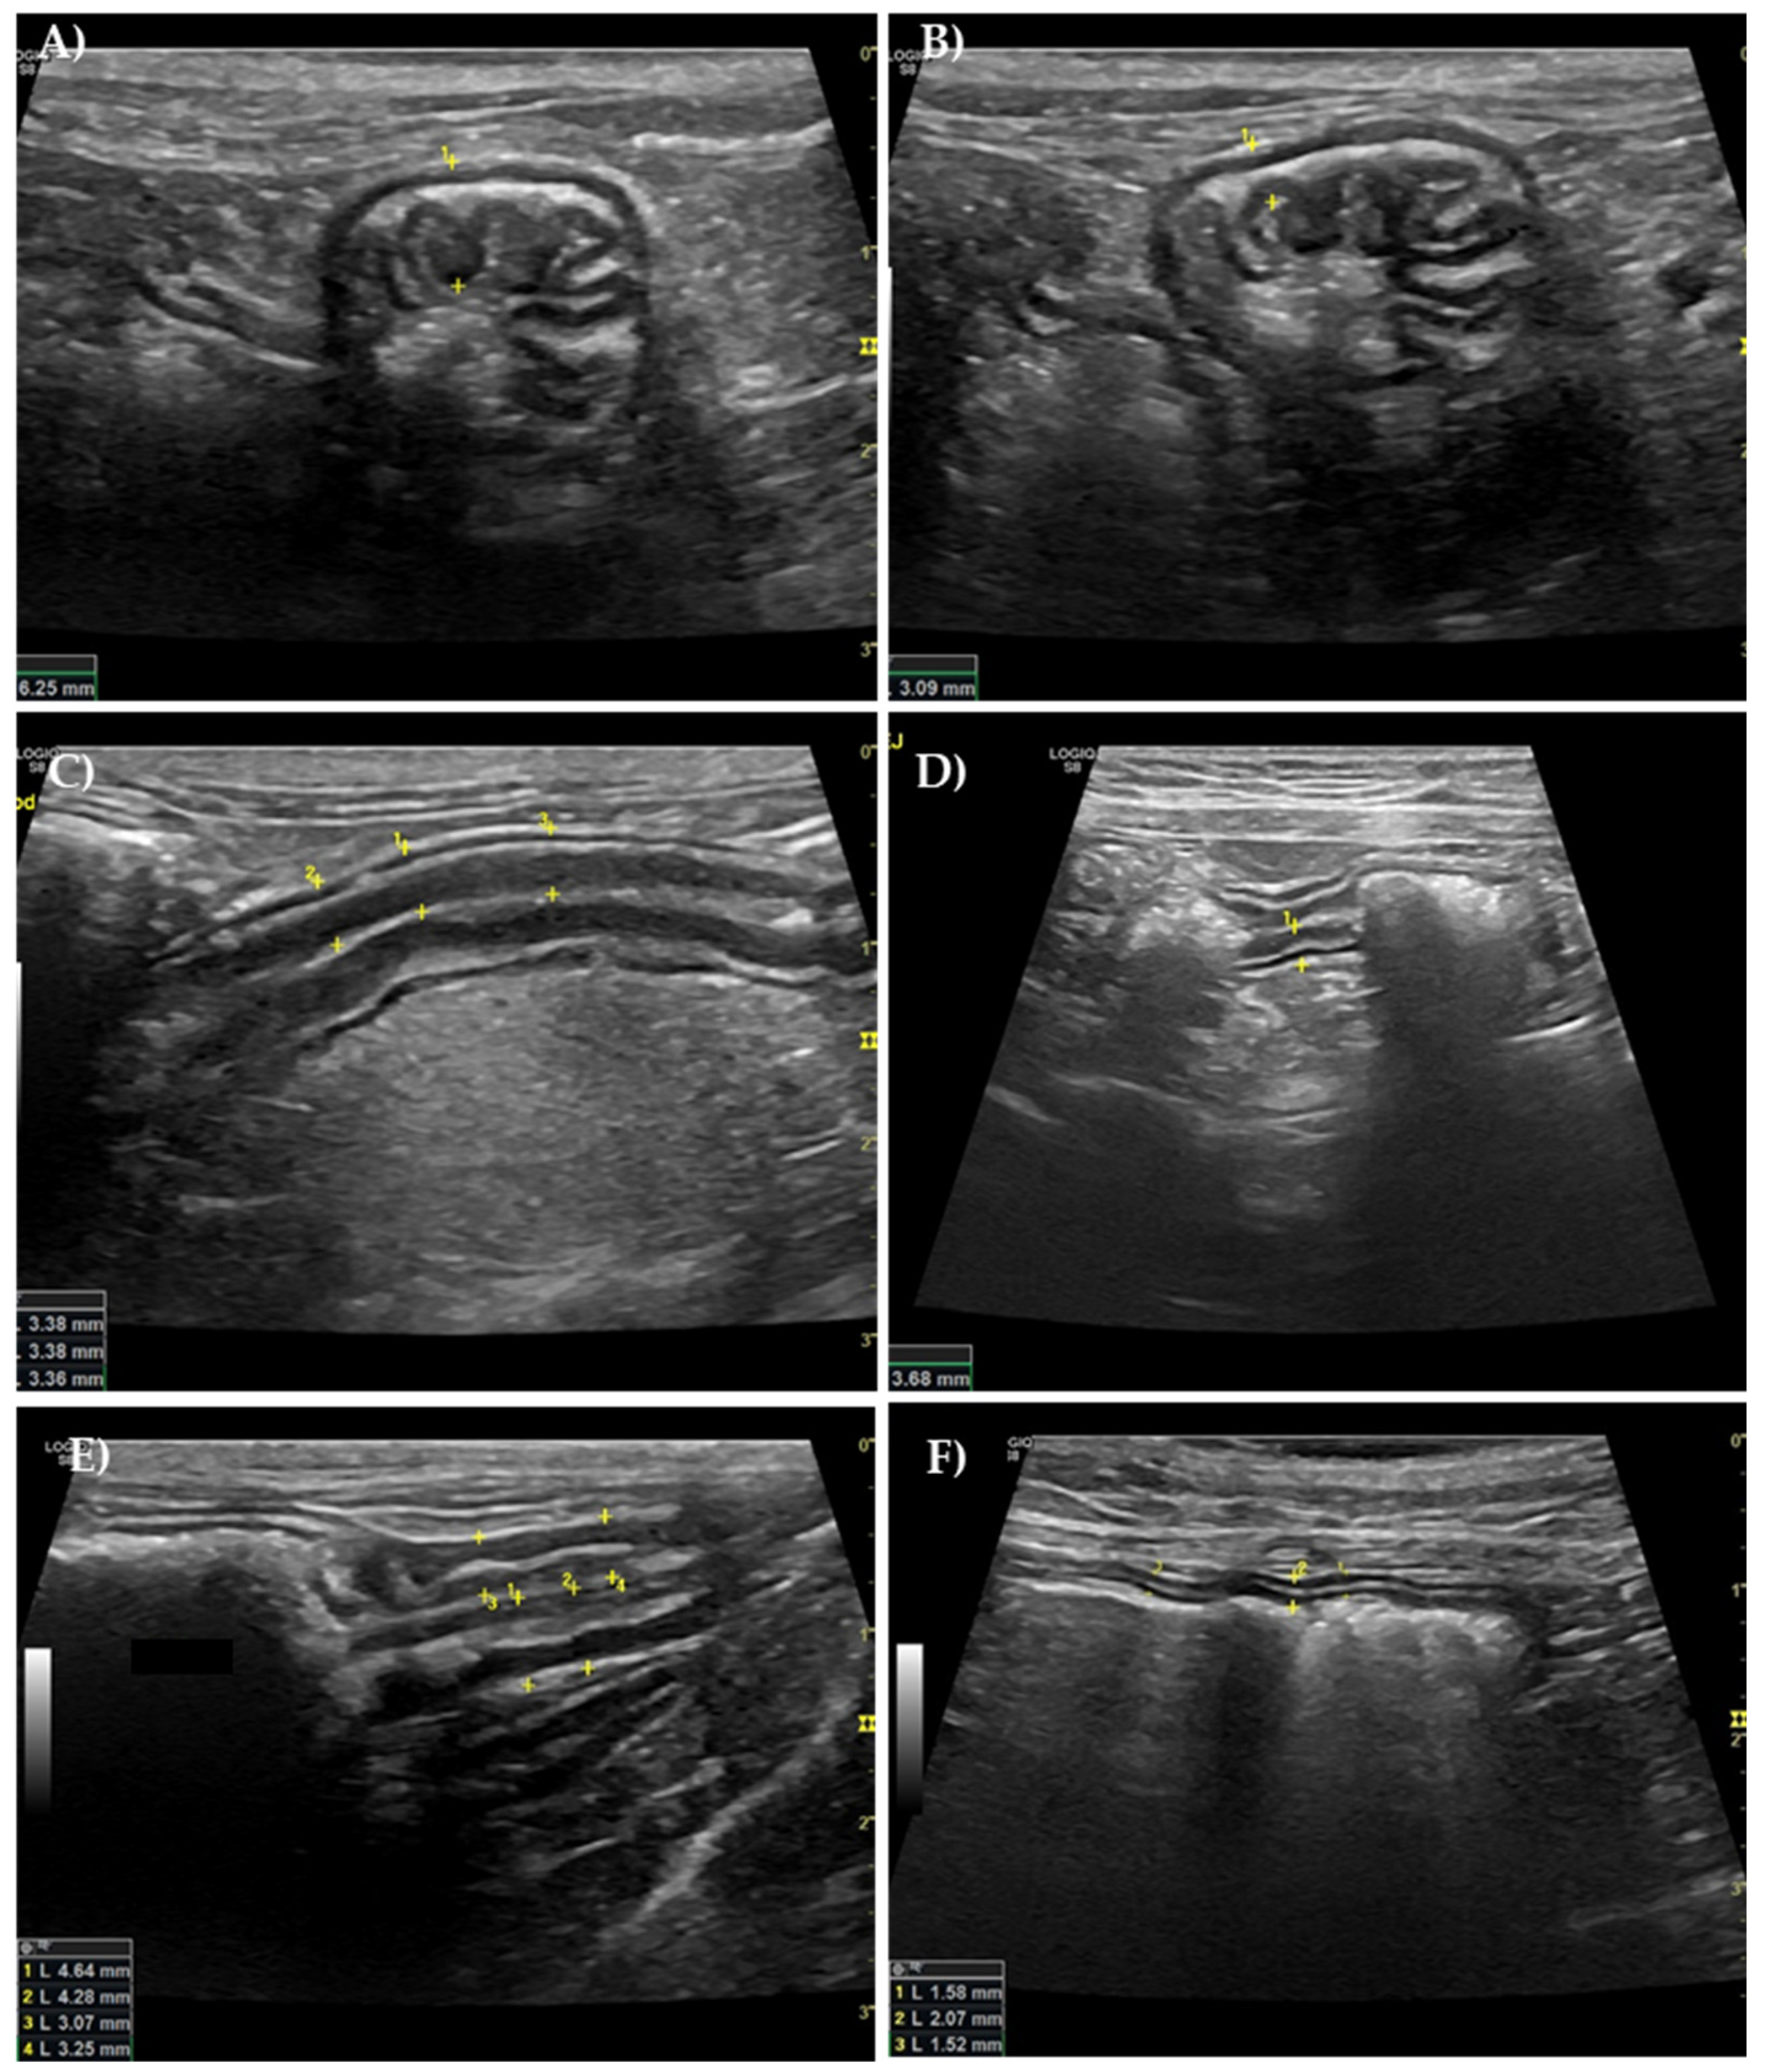

2.3. Ultrasound Evaluation of the GI Tract

3.3. Ultrasound Evaluation of the GI Tract